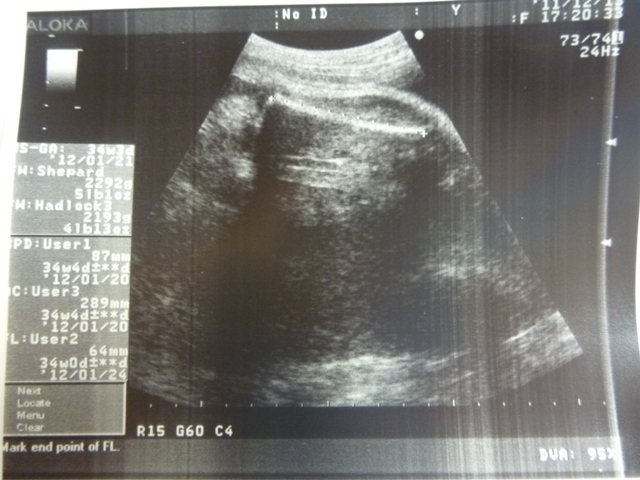

這是腹圍~~

這張是大腿骨長~

以以上三個Data來預估~

今天小貝果體重:估約2193~2292g

是週數的正常大小~